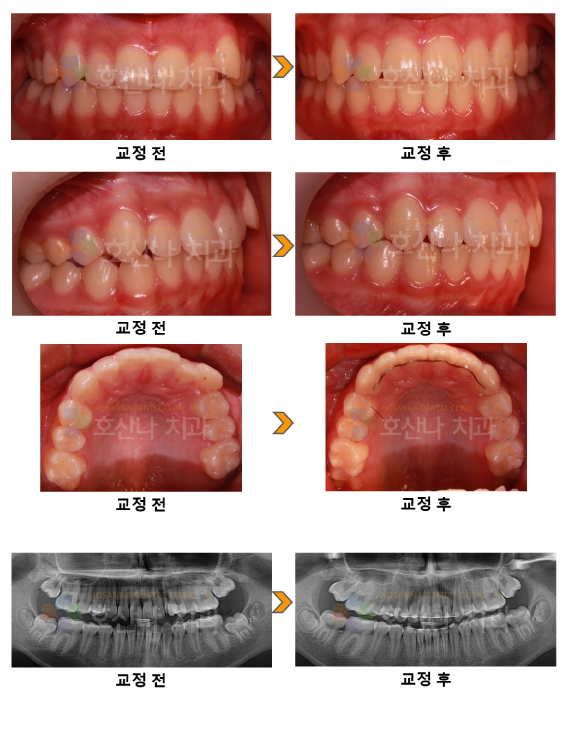

교정 비수술 돌출입교정 시술 증례

< 비수술 돌출입교정 시술 증례 >

1. 치료대상

10대  female

2. 교정치료이유

덧니 개선 원함

3. 진단결과

1) Skeletal CL I

2) Midline off

3) Dental RtCII Lt CII

4. Dr.Koo Memo

본 환자분은 예쁜 안모를 가진 10대로 최대한 발치 없이 교정을 원하셨고 진단을 통해서도 안모의 후퇴시

비심미적일것으로 예상하여  상악의 후방견인을 통해 안모가 지나지게 들어가는 것을 주의하여

교정을 마무리 하였습니다.

1년정도의 기간동안 비발치를 통해 가지런한 치열을 얻었습니다.

5.교정기간

1y 2m